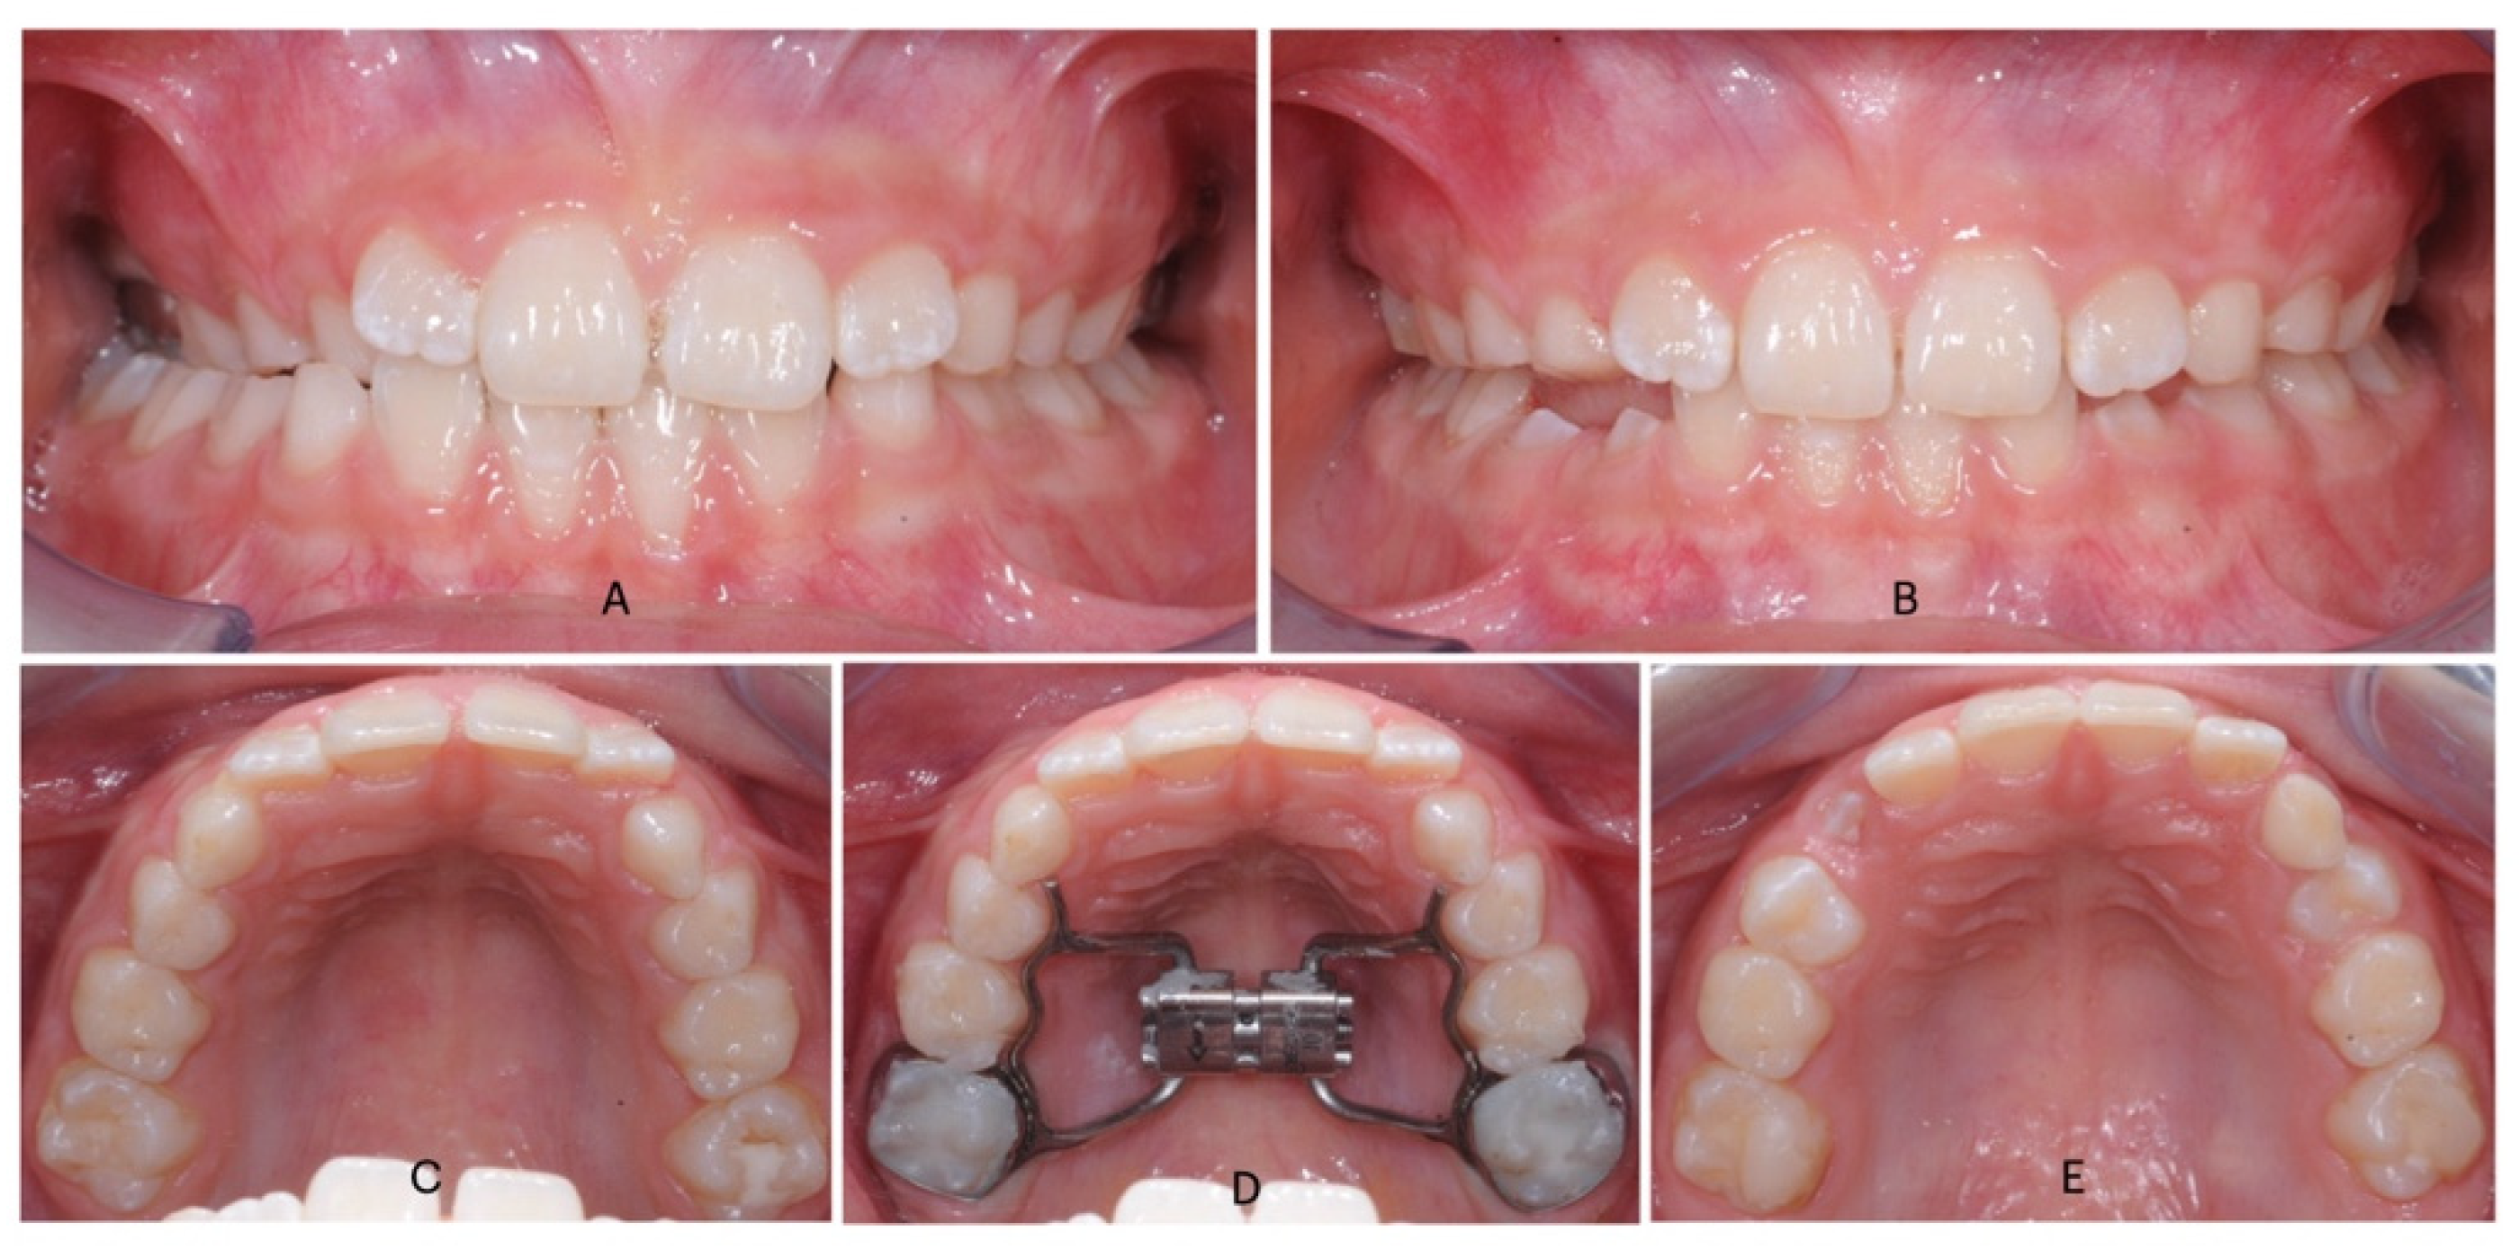

Figure 2.

Intraoral photos of Invisalign first treatment in a patient with a contracted upper arch a no cross-bite: (A) (pre-treatment frontal view); (B) (post-treatment frontal view after Invisalign expansion protocol); (C) (pre-treatment occlusal view); (D) (post-treatment occlusal view).